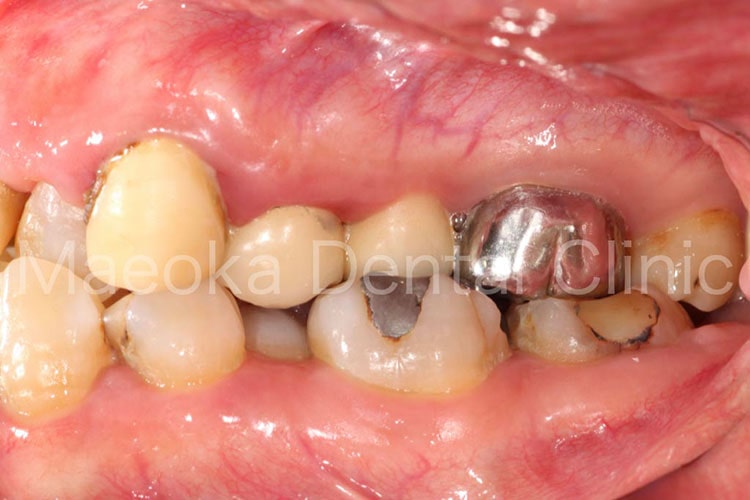

Case4

患者さんは58歳の男性の方で、「右下の歯がグラグラして痛いので診て欲しい」という主訴で来院されました。お口の中を拝見すると重度の歯周病を認めました。1日1箱近い本数の喫煙があったこともあり、歯肉は血行不良を起こして黒っぽい印象がありました。

初診時には歯周病の原因と「どうすれば歯周病は治るのか」、「再発を防ぐためには何が必要なのか」を説明し、歯磨きのトレーニングをスタートしました。その後、患者さんのプラークコントロールレベルが向上したタイミングで歯石を取り、基本治療を終えました。その後、義歯を入れるなどの機能回復も検討しましたが、患者さん自身が不都合を感じていなかった点、レントゲン上でも残存歯の負担が増加している所見が見られなかった点を考慮し、経過観察としています。

主訴の右下7は失うことになってしまいましたが、その他の歯は現在のところ1本も失うことなく経過しています。現在も喫煙はありますが、歯肉は引き締まり、健康な組織を取り戻しています。今後はメインテナンスを通してプラークコントロールレベルの維持に患者さんと取り組んでいきます。

初診時の右下大臼歯部

右のボタンをクリックすると表示されます。

治療前(正面)

治療後(正面)

治療前(右側方面)

治療後(右側方面)

治療前(左側方面)

治療後(左側方面)

治療の詳細解説